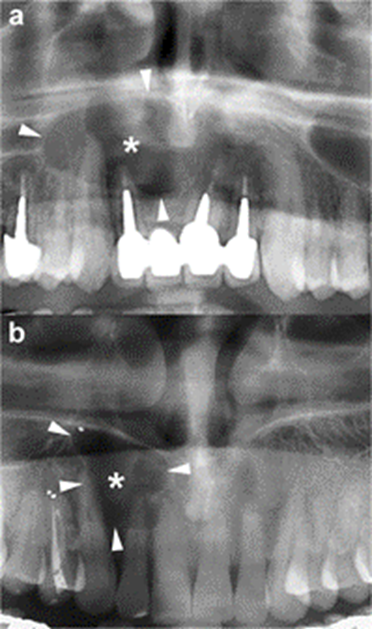

The radiographic features of OKCs are not pathognomonic, particularly in smaller unilocular lesions [15]. When a small unilocular OKC occurs in the anterior sextant of the maxilla, it may simulate other odontogenic and non-odontogenic cysts, such as radicular cyst (Figure 3), lateral periodontal cyst or nasopalatine cyst [17, 30].

Histologically proven OKCs. Cropped panoramic radiographs (a and b) show two unilocular radiolucent lesions (asterisks) with well-defined and

corticated margins (arrowheads) located in the anterior maxilla, between the roots of the adjacent teeth. The radiographic aspect of these radiolucent lesions may simulate a radicular cyst